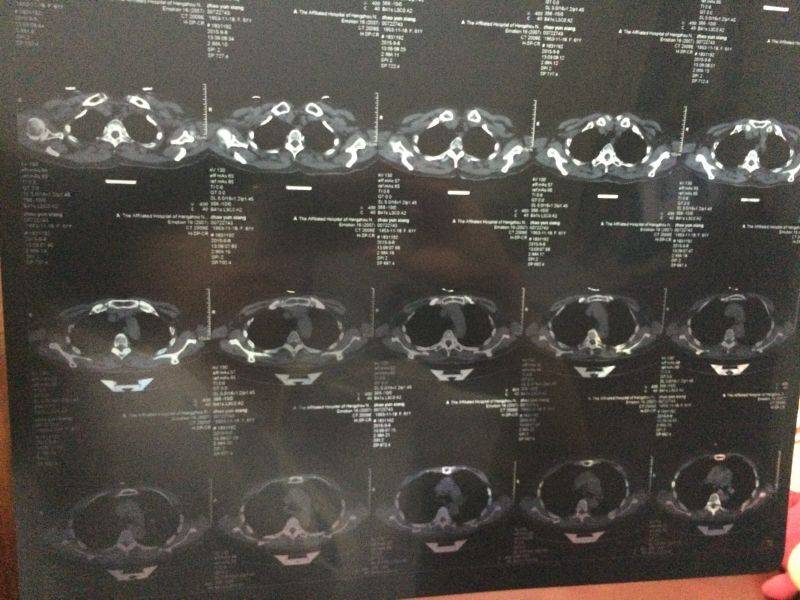

这个具体的情况是如何的人,谁帮忙看看?

为什么不去取活检,确诊病情,就这么出院了?从病历上看,还是比较乐观的,建议到医院进一步确诊。个人建议

病情的确诊最好是取活检确诊,进一步做检查吧

到医院做一个确诊,尽早的接受治疗